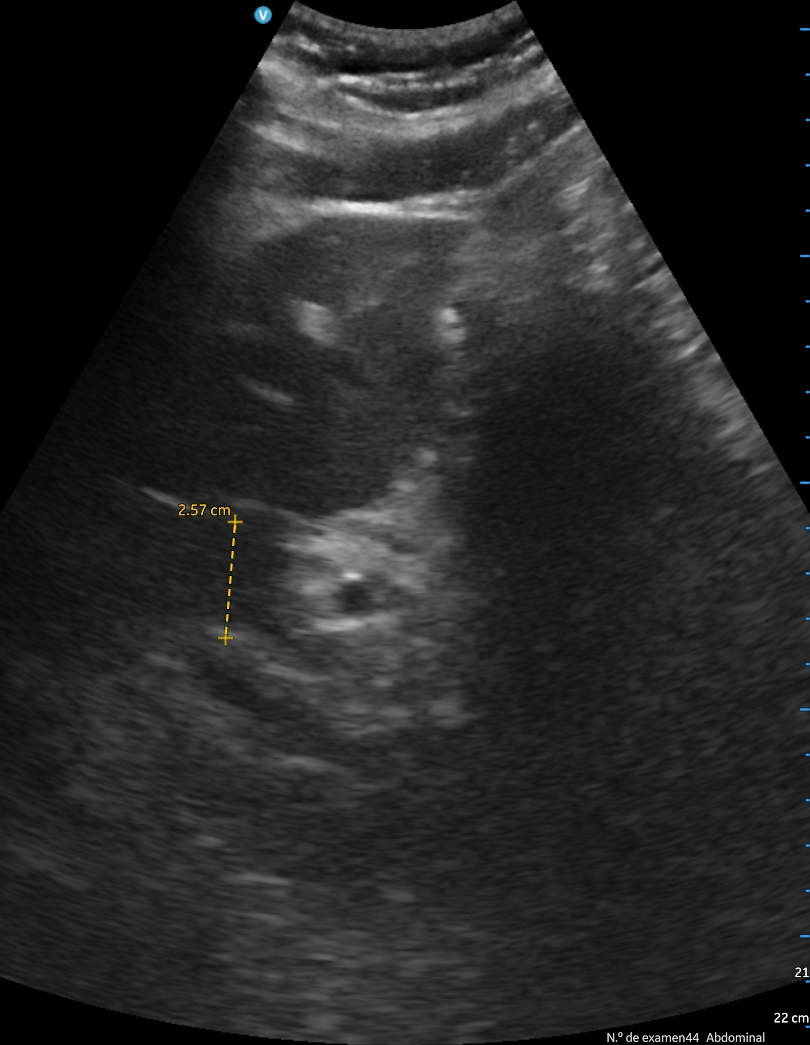

Se aprecia atelectasia lobar media con derrame pleural derecho de unos 150 cc, signo de la medusa. Líneas B en patrón B3 en ambas bases. Cavidades cardiacas normales con correcto funcionamiento valvular, adecuada contractilidad sin indicios de derrame pericárdico. Aumento de vena cava de 2,57 cm no colapsable.